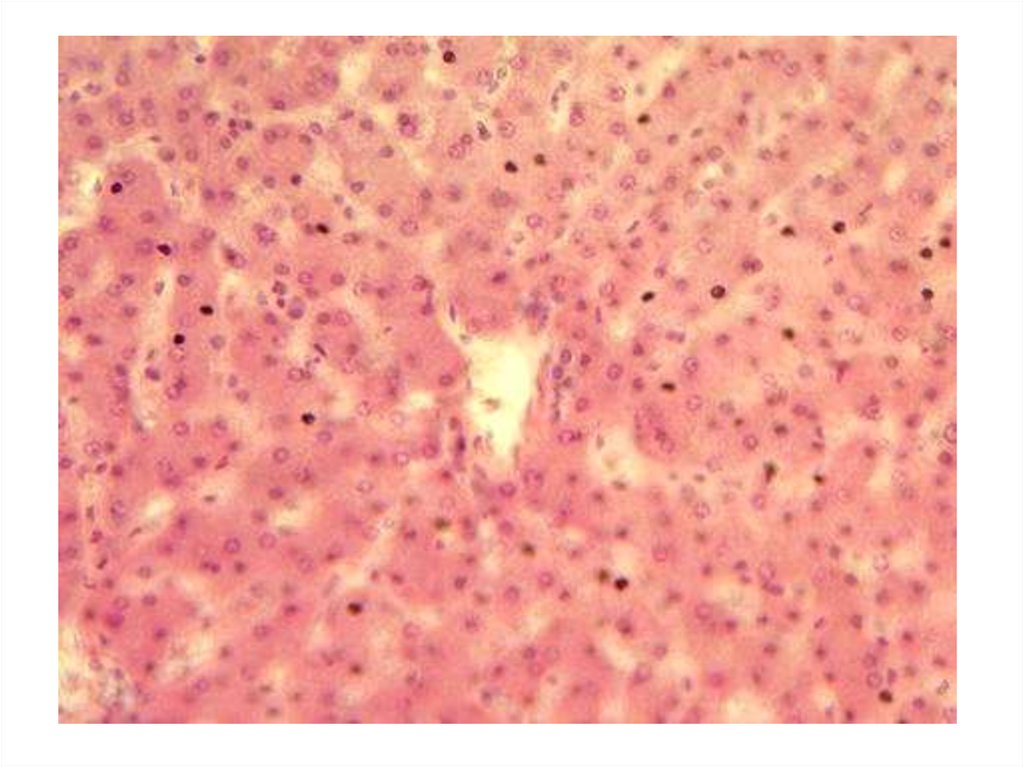

biology

Срезы тканей